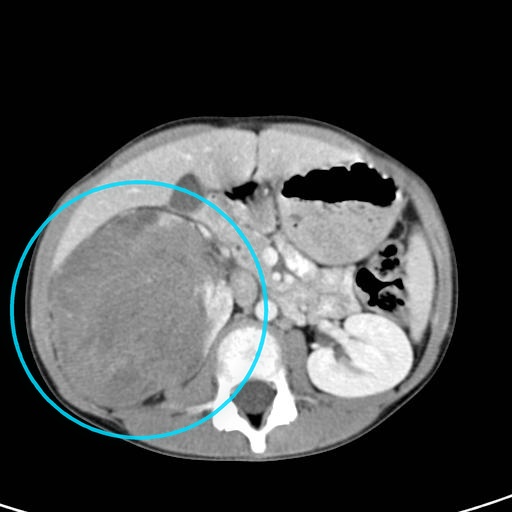

What's the Diagnosis?

Guess 1 / 5